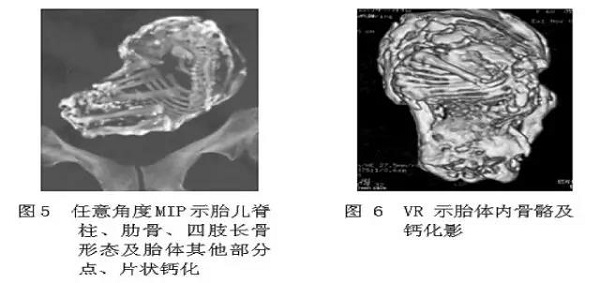

石胎的主要诊断手段是影像学检查,包括 B 超,X 线和 CT 等。超声下可见高回声光团和胎儿结构回声,X 线可以看到胎头、脊柱、肋骨及四肢等结构,CT 表现可见钙化的胎膜和胎儿(见下图)。

通常来说,B 超、X 线和 CT 可以满足需要,但仍然有局限性,有时不能很好的显示脊柱,肋骨和四肢的结构,或者石胎钙化不典型,存在误诊的可能。

石胎与畸胎瘤 B 超检查中有相似的声像图特征,也容易导致误诊。X 线为重叠图像,表现为团状钙化肿块,难以辨别脊柱、肋骨的影像。

鉴别诊断有难度时,可以考虑进行多层螺旋 CT(MSCT)扫描,更能直观、多方位、多角度地显示脊柱、肋骨、四肢及胎膜钙化情况,为临床提供准确的影像信息(见下图)。

图片来源:吴德红等. MSCT 对腹腔石胎的诊断价值. CT 理论与应用研究, 2015, 24(1): 129-134.